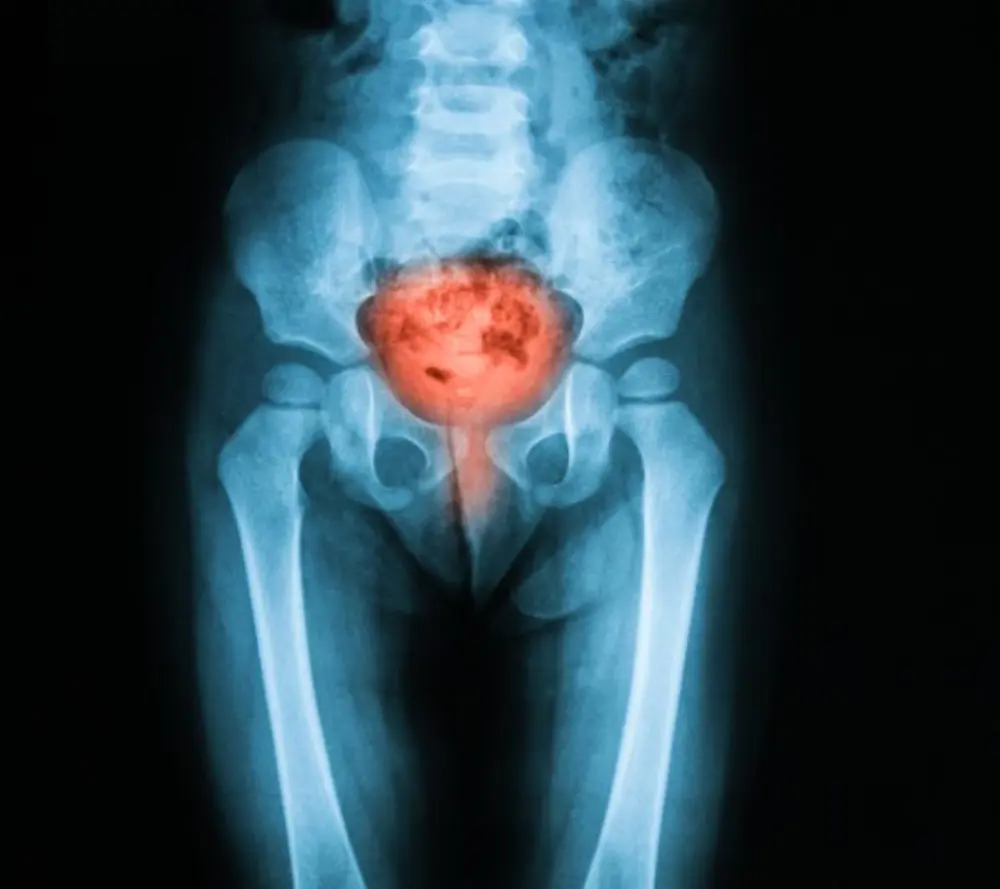

ما هو التهاب المثانة وحرقان البول؟

حرقان البول هو الإحساس بألم أو حرقة أثناء التبول، وذلك نتيجة عدة مشكلات صحية أهمها والأكثر شيوعًا هو التهاب المسالك البولية السفلية، أو ما يُعرف بالتهاب المثانة، حيث أن التهاب المثانة هو أحد أنواع عدوى المسالك البولية الشائعة والتي تحدث عادةً بسبب انتقال بعض البكتيريا المتواجدة بشكل غير ضار على الجلد أو في الأمعاء إلى مجرى البول والمثانة.

يصيب التهاب المثانة الرجال والنساء، ولكنه أكثر شيوعًا بين النساء لعدة أسباب منها أن مجرى البول قصير وقريب من فتحة الشرج، مما يجعل عملية دخول البكتيريا للمثانة أسهل، كما تتعدد أنواع التهاب المثانة نتيجة لاختلاف السبب، وتشمل ما يلي:-